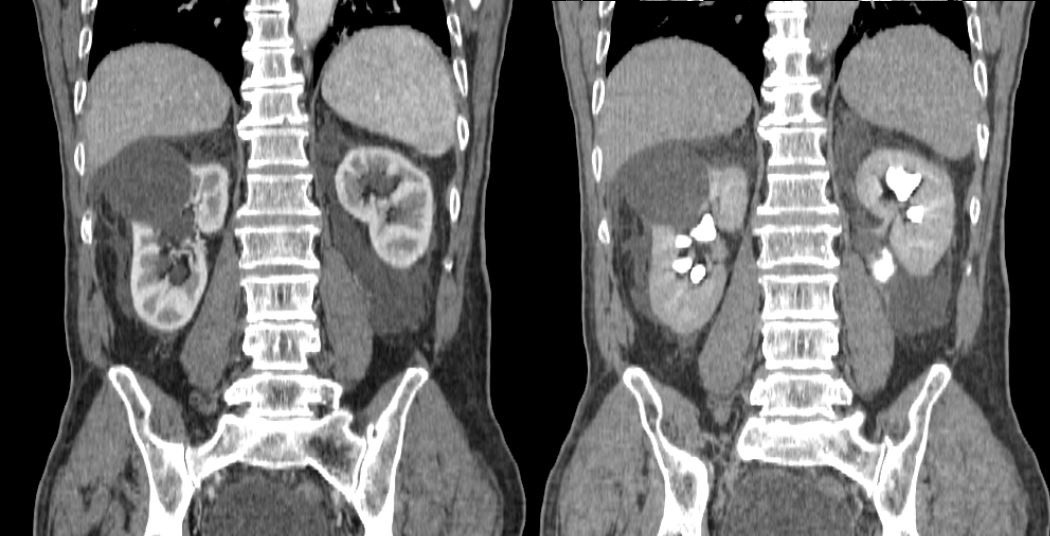

Following the intravenous contrast injection, in the post contrast series, the kidneys exhibited appropriate absorption and excretion of contrast media within the expected time frame (in a timely manner). However, it was observed that the patient had extrarenal pelvis bilaterally, cortical cysts bilaterally that didn’t interfere with the urodynamic, dilated ureters along with a dilated urinary bladder. Furthermore, in the adjacent kidney tissue, there was observed leakage of the contrast media from the renal pelvic lesions in both kidneys. There were no indications of trauma to the parenchymal organs within the abdominal region.

Figure 1. Free fluid in the surrounding kidney tissue.

Figure 2 and 3. As seen on the scans to the left, the surrounding free fluid dif. dx can mean urine, blood. On the scans to the right, the contrast media leakage is evident in the surrounding tissue, meaning there are lesions in the renal pelvis bilaterally.